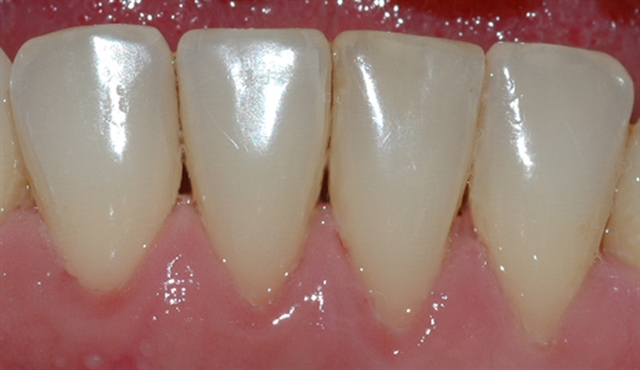

Bildet viser et tannsett med synlig tannsten og misfarging.

Bildet viser et nærbilde av tennene i underkjeven med tannsten og misfarging.

Bildet viser forholdene i underkjeven etter at tannsten og misfarging er fjernet